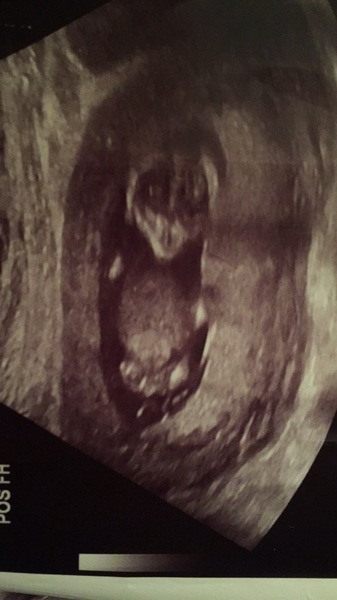

Here's one of the front facing shots we got Shock pointy little chin. Like an alien!

Wow Parney that's so cool! Never seen one like that before.

Wow @Parney what a great angle!!!

@Parney that pic is amazing ....never seen that angle before!

Thanks @olicat, @fitbit, @thelostsock, @MrsD and @Boat. It is a funny angle! We got DS like that at 20 weeks too so it must be something to do with my uterus Hmm he had a much wider jaw line, wondering if this is a girl or maybe a lot of filling out happens between now and 20 weeks.